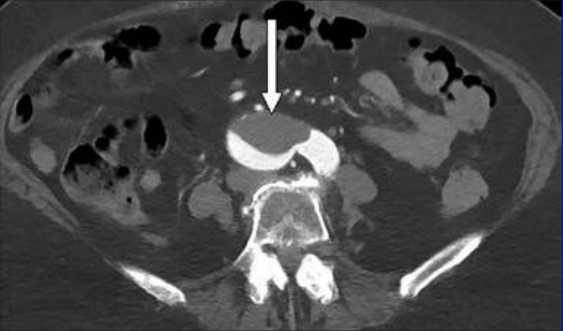

This photo gallery shows the variety of radiological presentations of COVID-19 (SARS-CoV-2) in medical imaging, including computed tomography (CT), radiograph X-rays, ultrasound, echocardiograms and magnetic resonance imaging (MRI). The radiology images show examples of typical COVID pneumonia in the lungs and the numerous complications the virus causes in the body in multiple organs, including the brain, kidneys, heart, abdomen and vascular system.

Ultrasound, especially hand-held ultrasound imaging devices, have become a primary imaging modality for novel coronavirus because of the ease to bag the device and sterilize it after use. CT and mobile X-ray systems are also used as front-line imaging systems for COVID-positive or suspected COVID patients.